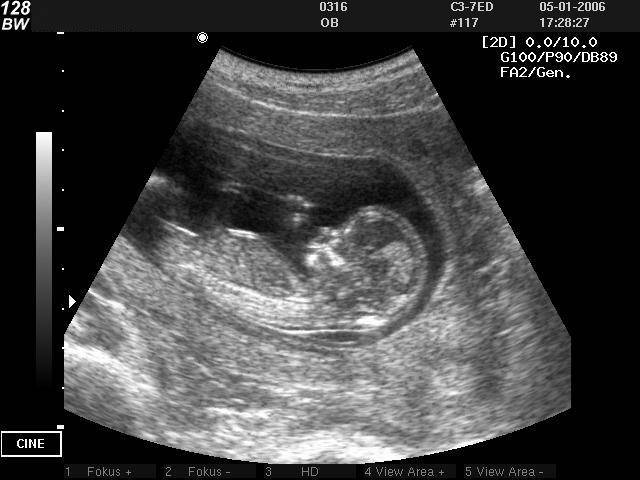

Как определяется продолжительность вынашивания с помощью УЗД?

В первые 3 месяца, когда эмбриона разглядеть невозможно, специалисты узнают по рассчитываемому СВД плодного яйца – среднему внутреннему диаметру. Этот параметр определяется по нижеуказанному алгоритму:

- осуществляется измерение переднезаднего и продольного размеров плодного яйца при продольном сканировании;

- выполняется замер ширины при поперечном сканировании;

- из полученных чисел рассчитывается среднее арифметическое.

В 5,5 нед. для среднего внутреннего диаметра характерны значения от 0,6 до 0,7 см. С каждым днем эмбрион растет при нормально развивающейся беременности:

- в 6 нед. рассматриваемый показатель уже становится равным 1,1 см;

- в 6,5 нед. – 1,4 см;

- в 7 нед. – 1,9 см;

- в 7,5 нед. – 2,3 см;

- в 8 нед. – 2,7 см.

Когда начинает визуализироваться эмбрион, показателем, позволяющим узнать продолжительность периода вынашивания, становится КТР – размер, называемый копчико-теменным.

Определение КТР при УЗИ

Он определяется при сагиттальном сканировании. Под этим параметром подразумевается максимальное расстояние от копчика до наружного контура головного конца:

- в 1 мес. и 3 нед. КТР равен 0,81 см;

- в 2 мес. – 1,48 см;

- в 2 мес. и 1 нед. – 2,24 см;

- в 2 мес. и 2 нед. – 3,12 см;

- в 2 мес. и 3 нед. – 4,21 см;

- в 3 мес. – 5,11 см;

- в 3 мес. и 1 нед. – 6,32 см;

- в 3 мес. и 2 нед. – 7,67 см.

Как устанавливают срок беременности по УЗИ

Вне зависимости от того, с помощью какого датчика проводится исследование, врач-сонолог (специалист, который делает УЗИ) определяет срок беременности по размерам плода. У сонолога есть специальные таблицы с нормативными показателями. Врач сравнивает данные, полученные в ходе обследования, с данными в таблице, и на их основании делает вывод о сроке беременности.

До 10 недели определение срока основывается на вычислении длины эмбриона. На этом этапе погрешность диагностирования минимальна, не более 1-2 дней. Так как в первые месяцы после зачатия все эмбрионы развиваются с одинаковой скоростью. А вот начиная со второго триместра беременности, когда уже сформировалось тело маленького человечка, сонолог производит замеры копчико-теменного расстояния, окружности головы, длины трубчатых костей, диаметра грудной клетки, и на основании этих данных дает заключение о «возрасте» малыша. После 12 недели точность, с которой высчитывается продолжительность вынашивания малыша, уменьшается, так как каждый ребенок развивается и растет индивидуально, в зависимости от того, какие гены достались ему от родителей. Поэтому гинеколог, направляя женщину на УЗИ во втором или третьем триместре, учитывает эту погрешность. И если размеры малыша указанные в заключении сонолога больше или меньше нормы, но равны показателям соответствующим значениям предыдущей или следующей недели беременности, то это считается допустимым.